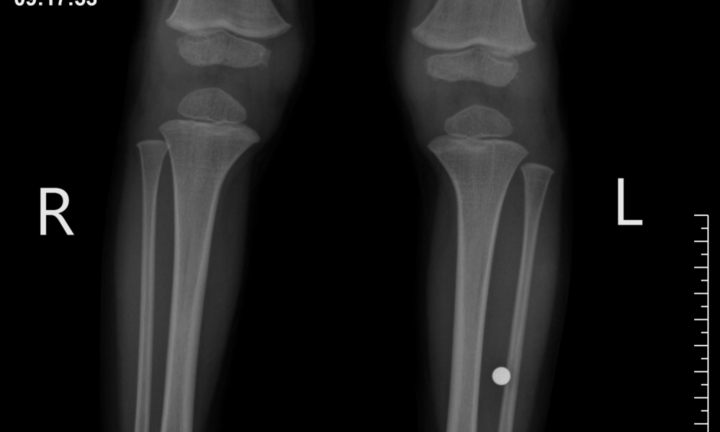

Hoảng loạn khi phát hiện viên bi đồ chơi trong chân bé trai 3 tuổi

Viên bi có đường kính 5mm nằm sâu trong cẳng chân của một bệnh nhi 3 tuổi tại Phú Thọ.